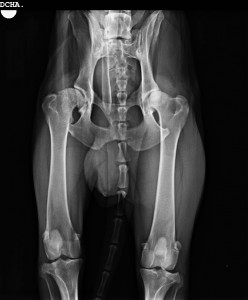

Esta es su Rx de cadera, en la que se vé la diferencia entre ambas articulaciones.